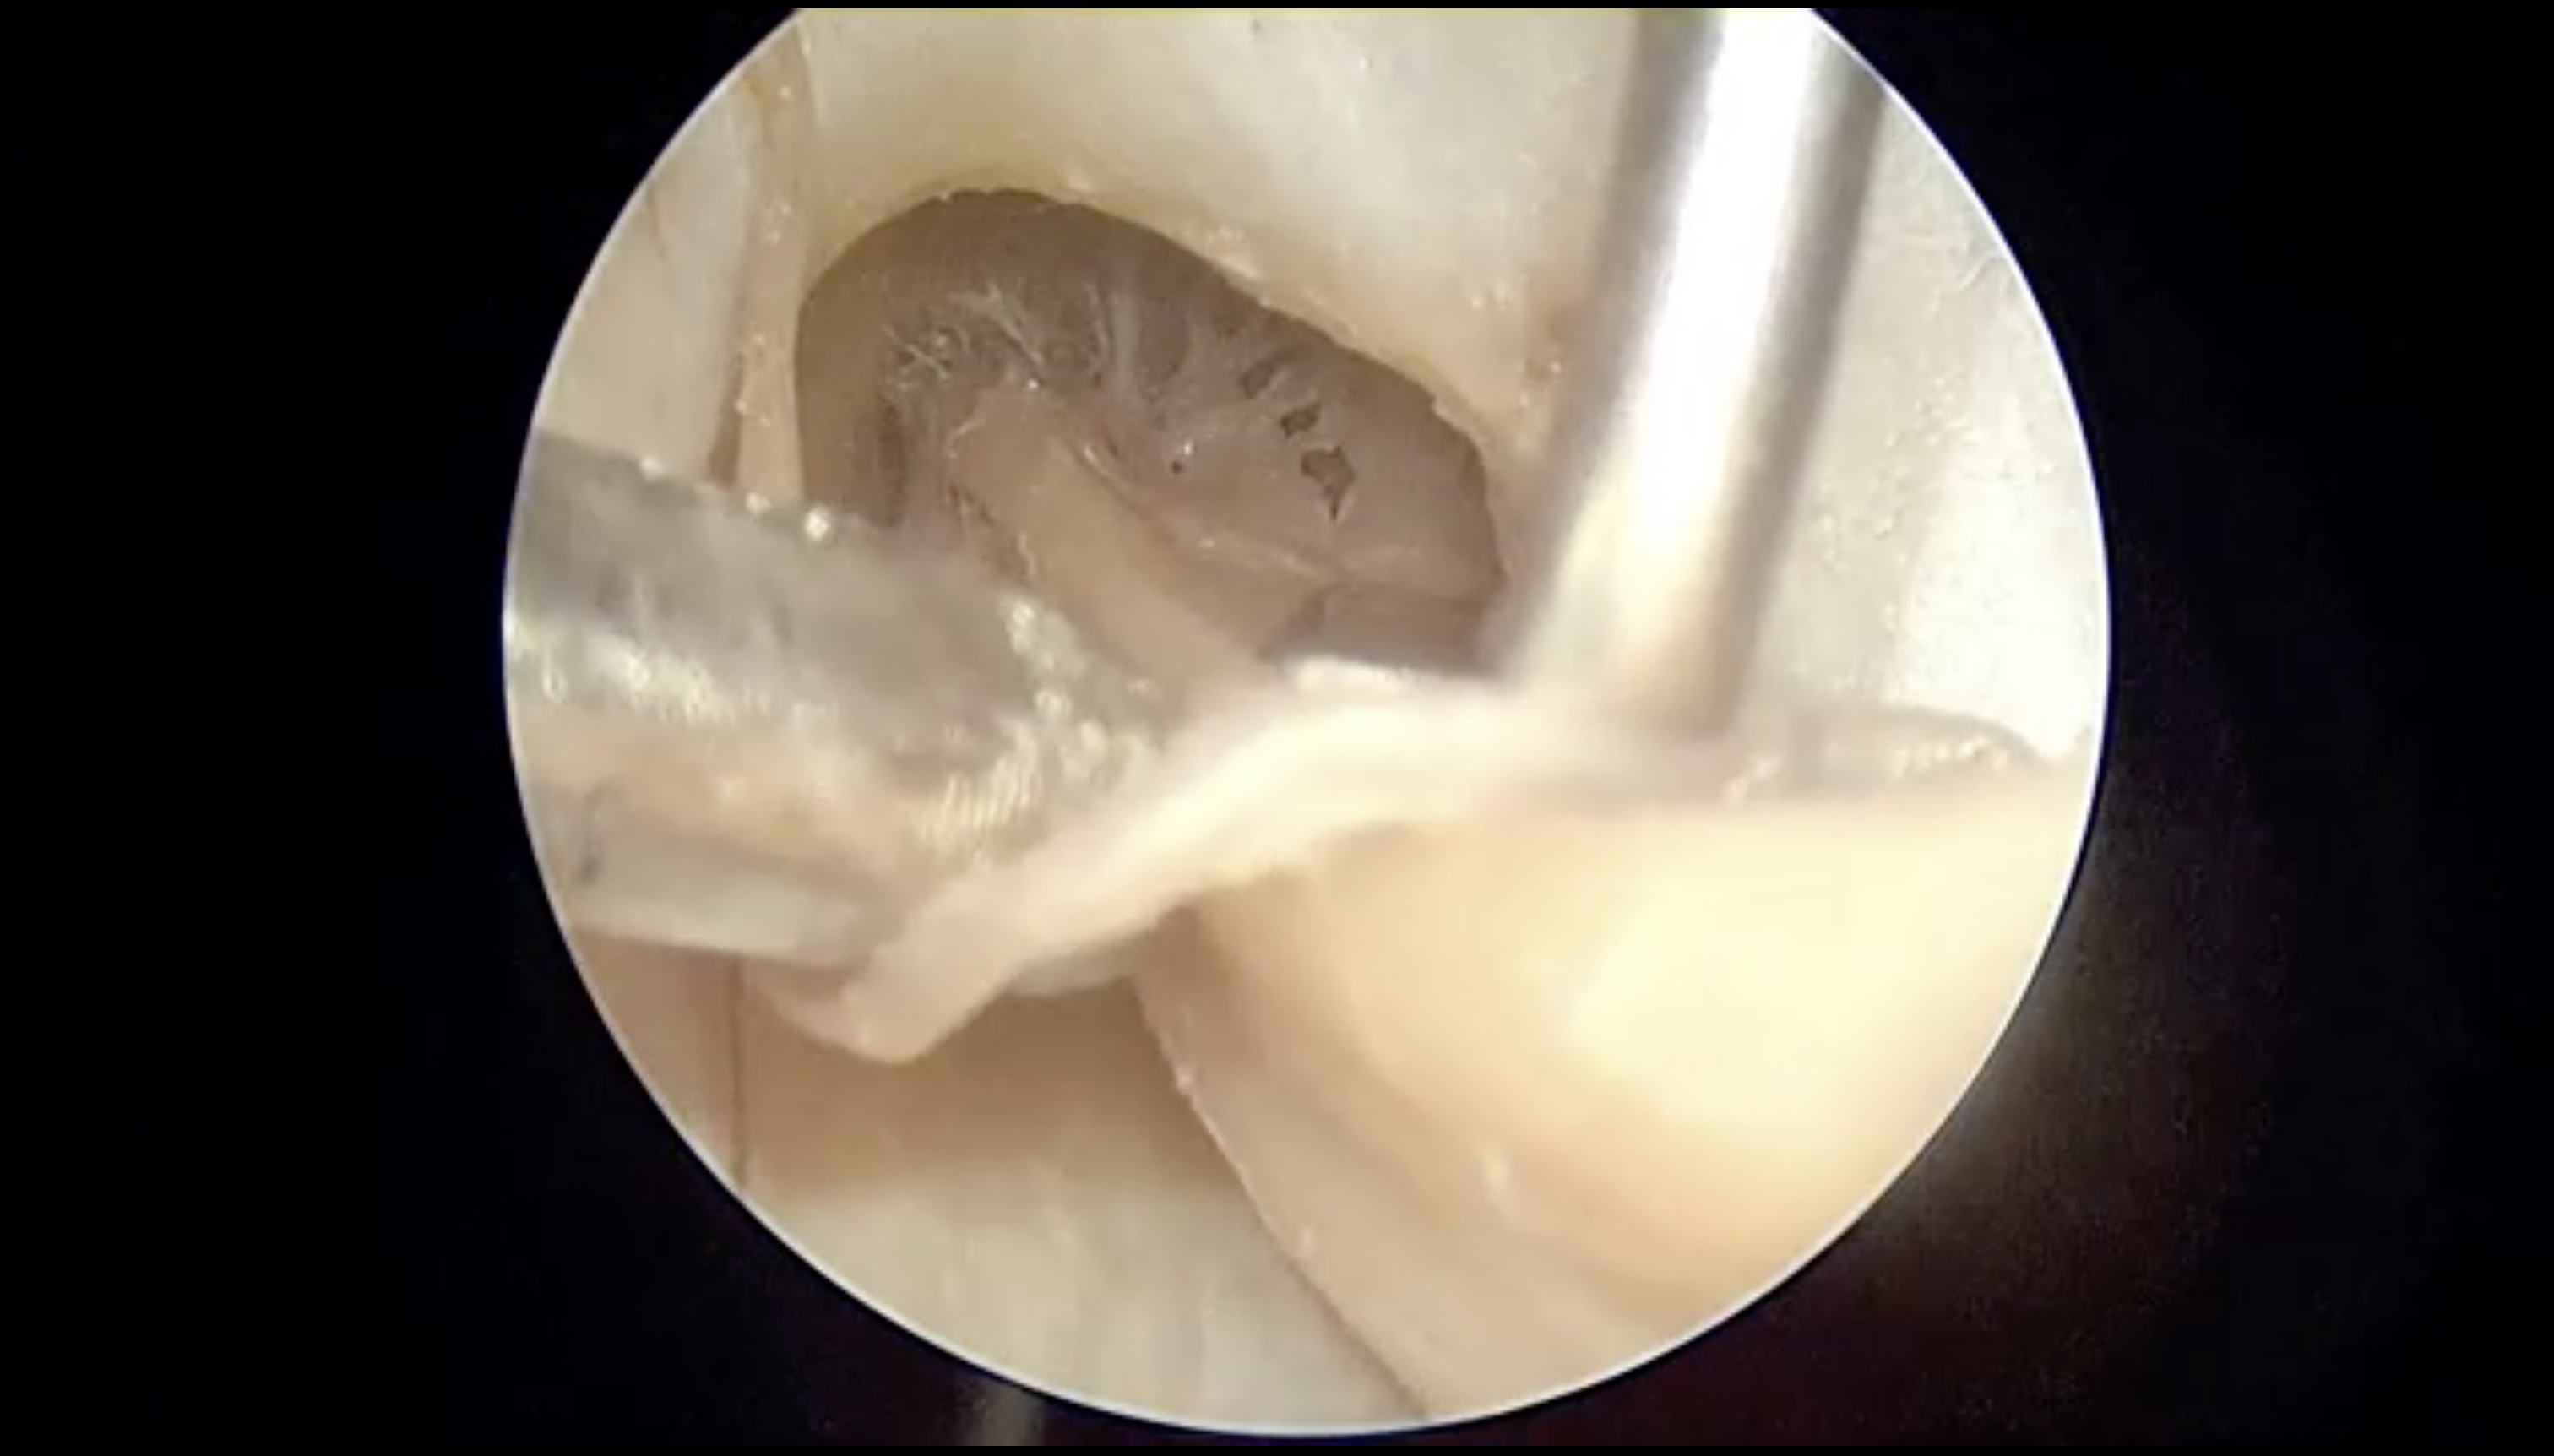

显微镜下全切内听道内听神经瘤